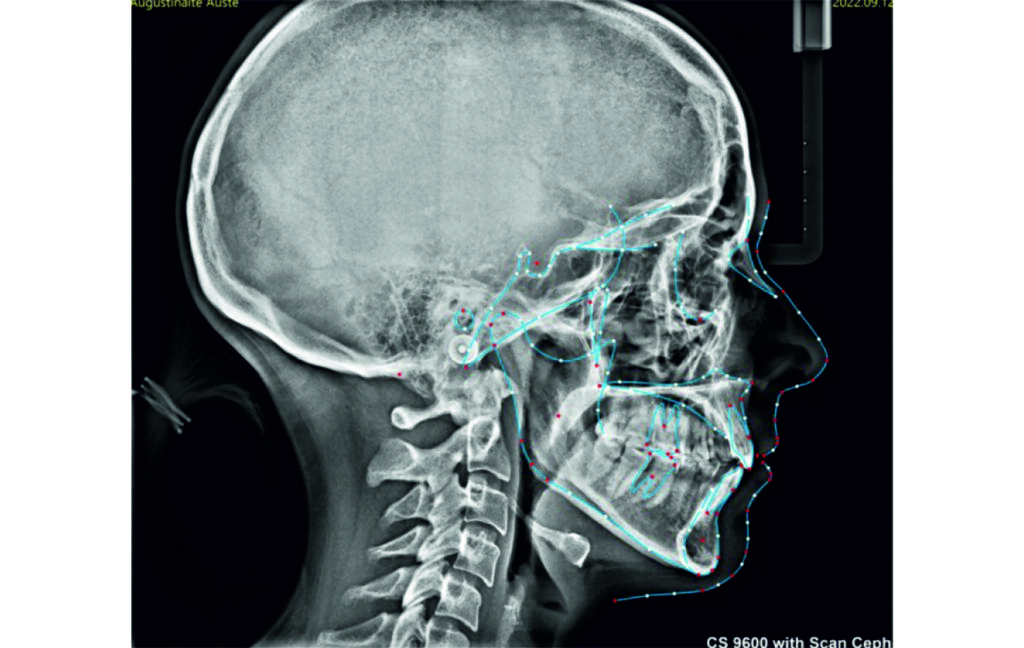

Initial Photos and datas

Angle Class II 2mm on the right, Angle Class II 2mm on the left, light mandibular asymmetry to the right, lower central line 1mm to the right, upper central line 1,5mm to the left, 1mm overjet and overbite. Sagittal asymmetry of upper dental arch. Light crowding upper and lower frontal segments, severe attrition of posterior teeth, night bruxism. Normal sagittal position of both jaws, high angle case, steep mandibular ramus,excessive lower facial height, open bite tendency.

Soft Tissue Analysis: convex profile, lower third of the face increased, slightly retrusive upper and lower lips, lip strain on closure.

An infrazygomatic crest (IZC) screw with force applied between the upper premolars produces a clockwise rotation of the maxillary occlusal plane. This movement aids in closing the anterior open bite and improves upper incisor display. IZC screws with elastics also enable planned intrusion of the upper molars by 1 mm. Because mandibular derotation after upper posterior correction is difficult to predict, anterior distalization and midline correction were performed in the later stages of treatment.